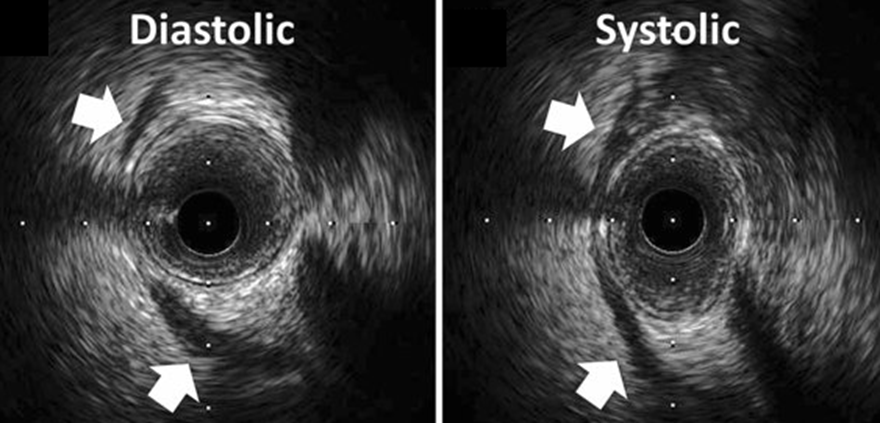

A myocardial bridge occurs when a segment of a coronary artery, most commonly the left anterior descending (LAD) artery, tunnels through the myocardium instead of resting on its surface. During systole, the heart muscle contracts, compressing the bridged artery and potentially impeding blood flow. This compression can lead to myocardial ischemia, manifesting as chest pain or even more severe cardiac events in certain cases.

• Intravascular Ultrasound (IVUS): Offers real-time imaging of the coronary artery, assessing the degree of compression and the length of the bridged segment.